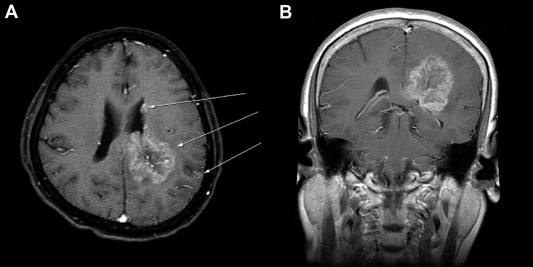

The patient experienced progressive recent and remote memory impairment and cognitive dysfunction 1 year after her diagnosis of breast cancer. She was also found to have mild weakness (motor grade = 4+/5) of the right upper and lower limbs. Cranial functions and other neurologic examinations were unremarkable. Further CT and MRI examinations of the brain demonstrated that the patient had multiple brain lesions, including a large (4 × 4 × 5 cm3 in size) brain tumor located at left parieto-occipital subcortical regions extending into the ipsilateral splenium of the corpus callosum, and two other small, but apart, lesions in the lateral ventricle wall and the parietal cortex of the ipsilateral brain (Fig. 1). The patient was diagnosed to have a multifoci primary brain malignancy rather than secondary metastases, because the largest brain lesion was relatively infiltrative and deeply invasive to the corpus callosum. She subsequently underwent a craniotomy for gross total resection of the largest brain lesion. Pathologic examination demonstrated the tumor to be an anaplastic oligodendroglioma with plenty of cells having hyperchromatic, pleomorphic nuclei and abundant pale eosinophilic cytoplasm, and with vascular proliferation (Fig. 2A). Further immunohistochemical examinations showed that the tumor was strongly positive for glial fibrillary acidic protein (GFAP) but was negative for cytokeratin staining (Fig. 2B and 2C). Moreover, the Ki-67 labeling index was found to be approximately 40% (Fig. 2D), indicating a relatively high mitotic activity. Furthermore, the methylation-sensitive polymerase chain reaction (PCR) of the tumoral tissues demonstrated the O6-methylguanine-DNA methyltransferase (MGMT) promoter of the tumor to be a methylated one (Fig. 3A). Capillary electropherograms of PCR products resulting from amplification of microsatellite loci on chromosomes 1p and 19q revealed that the tumor samples contained 1p/19q codeletion (Fig. 3B). The patient then received external beam radiotherapy up to 60 Gy with concurrent daily temozolomide treatment (75 mg/kg), followed by standard temozolomide monotherapy (200 mg/kg) for the subsequent 12 months. The patient tolerated the treatment well and made an uneventful recovery. Her Karnofsky performance scale was improved from a score of 60 to that of 70 after the neurosurgical treatment. In addition, she remained progression free and did not have notable intracranial recurrence up to 24 months after her brain surgery (Fig. 3C).

Magnetic resonance imaging of the patients brain. (A) Axial T1-weighted image ...

Figure 1.

Magnetic resonance imaging of the patients brain. (A) Axial T1-weighted image with gadolinium enhancement shows a large left-sided parieto-occipital lesion, located at the subcortical region but extending into the ipsilateral corpus callosum, and two concurrent small lesions in the ipsilateral lateral ventricle wall and parietal cortex (arrows). (B) Coronal section of the largest lesion shows compression of the left lateral ventricle and extension into the corpus callosum.

In this case, we could not exclude completely the possibility that the other two small nodules observed in the ipsilateral contiguous cortical and ventricular regions, as seen in Fig. 1, were actually metastatic lesions originated from her breast cancer. In a follow-up period of 2 years, the patient, however, did not have notable metastatic lesions from her breast cancer. A high mitotic activity of the anaplastic oligodendroglioma, as evidenced by 40% of the Ki-67 labeling index, also suggested a relatively high risk for developing early intracranial seeding of the anaplastic oligodendroglioma along the white matter and CSF pathways. Alternatively, it was also likely that this multifocal tumor had phenotypes derived from different progenitor cells of tumors (polyclonal origin). A favorable outcome observed with the patient, however, support that the presence of intracranial tumor dissemination on initial diagnosis does not, in itself, preclude aggressive treatment for high-grade glioma if a patient is otherwise well.